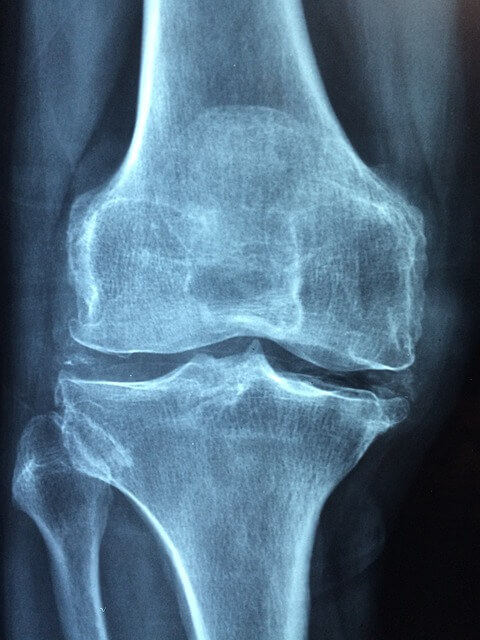

시서스는 특히 관절 및 연골 건강에 도움이 되는 것으로 알려져 있습니다. 일부 연구에 따르면, 사각 말린드나무는 관절염 및 골다공증과 같은 자주 발생하는 섬유염 관절 질환에서 두통, 염증 및 아픔 완화 도움을 줄 수 있습니다.